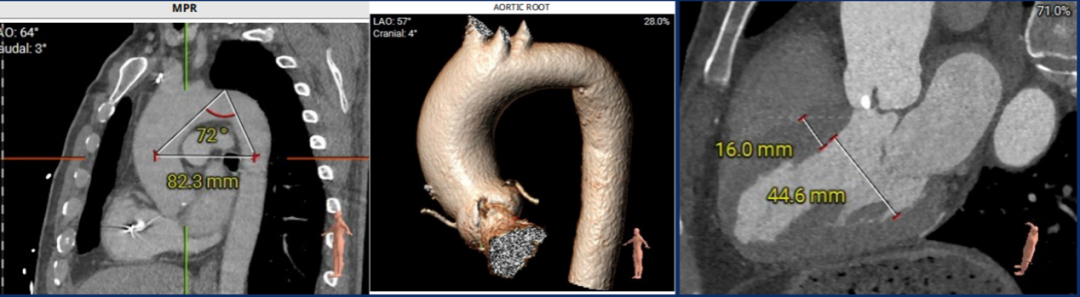

CT结果:

根据杭州方案, 针对BAV伴严重钙化的患者,提出采用球囊预扩张辅助测量瓣上结构,并根据瓣环直径选择不同尺寸球囊。若球囊扩张时出现“腰征”且无反流,可考虑选择稍小的人工瓣膜(Downsizing),并建议较高位置植入以优化治疗效果。术前CT评估显示患者为0型二叶式主动脉瓣(BAV)伴严重钙化。根据杭州方案,团队决定采用基于瓣上结构的尺寸选择策略,最终选用Evolut Pro瓣膜系统,配合23 mm Z-Med球囊进行预扩张。